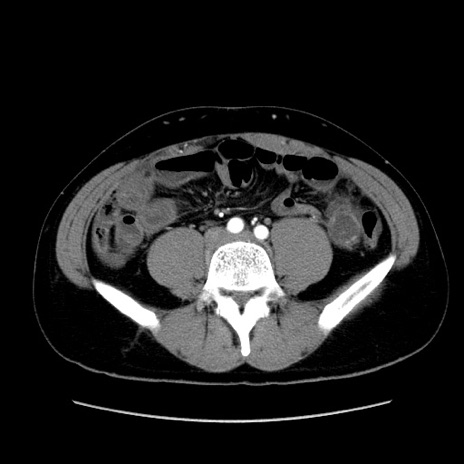

症例36(横断像)

【症例】20歳代 男性

【主訴】心窩部痛

【現病歴】今朝より上腹部痛あり。一旦軽快していたが再度出現したため救急要請。昨日夕に白身の魚を含む刺身を食べた。

【身体所見】BP 136/89mmHg、HR 74/min、BT 37.0℃、腹部:膨満、軟、心窩部に圧痛あり。反跳痛なし、筋性防御なし、腸雑音やや亢進あり。

【データ】WBC 17700、CRP 0.48